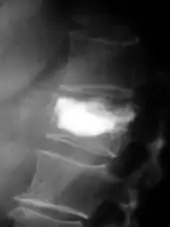

Rayons X

Pour le diagnostic initial, la radio X classique a une importance centrale. L'indication pour des projections sur deux plans est toujours donnée en cas de soupçon de tumeur osseuse[87]. Les métastases ostéolytiques sont caractérisées par une perte de densité osseuse. Ceci se reconnaît sur la radio par un noircissement plus élevé, en raison de la plus grande transparence aux rayons X. Inversement, les métastases ostéocondensantes présentent à cause de la plus grande densité osseuse un noircissement inférieur. Les métastases ostéolytiques sur la colonne vertébrale sont nettement plus difficiles à reconnaître : seulement quand environ 50 % de la densité totale de l'os a disparu[87].